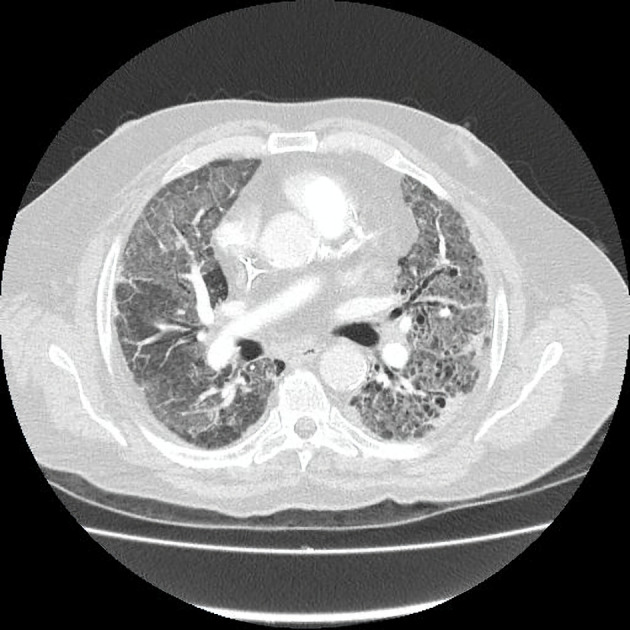

Immune checkpoint inhibitors like pembrolizumab represent a modern approach to the management of various malignancies, including non-small cell lung cancer. The therapeutic activity of immunotherapy is exerted by the activation of immune cells against the tumor cells. However, systemic activation of the immune system can lead to the development of autoimmune complications known as immune-related adverse events. A combination of rare immune-related adverse events is occasionally observed simultaneously in the same patient. We present the case of a 66-year-old male with squamous non-small cell lung carcinoma who presented to the emergency department with dyspnea and respiratory failure. Imaging findings were consistent with pulmonary embolism and nonspecific interstitial pneumonitis. One month before this event, he was diagnosed with bullous pemphigoid following 21 cycles of treatment with pembrolizumab. The radiological findings, the lack of response to antibiotics, the negative microbiological workup, and the excellent response to corticosteroids established the diagnosis of pembrolizumab-induced pneumonitis. The combination of bullous pemphigoid and pneumonitis secondary to pembrolizumab is rare; only a few case reports exist in the literature. Hence, this case highlights the possibility of multiple immune-related adverse events in the same patient. The exclusion of infectious diseases and other immunologic disorders with a similar clinical presentation is necessary to make the final diagnosis of immune-related adverse events and start the appropriate treatment. Serology, histopathology, and direct immunofluorescence aid to the diagnosis of immune-related bullous pemphigoid; the differential diagnosis includes other pemphigoid or lichenoid diseases, Stevens-Johnson syndrome/toxic epidermal necrolysis, and drug reaction with eosinophilia and systemic symptoms. Imaging, microbiological testing, and bronchoscopy (if possible) confirm the diagnosis of immune-related pneumonitis, which should be differentiated from acute coronary syndrome, cardiogenic pulmonary edema, pulmonary embolism, tumor progression, and lower respiratory tract infections (especially Pneumocystis jirovecii pneumonia in immunocompromised patients). An interdisciplinary approach is necessary for the management of these cases.